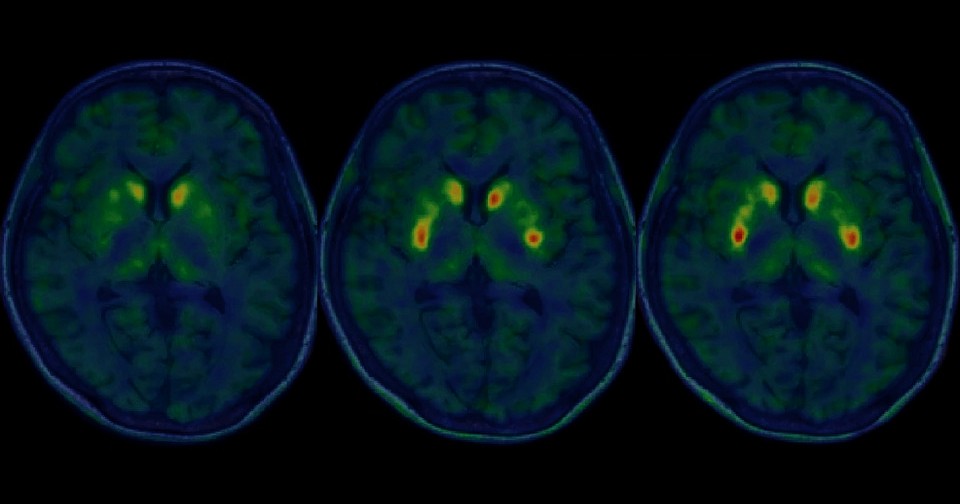

Основанием для одобрения стали результаты открытых нерандомизированных испытаний фазы I/II. В ходе них семь пациентов (возраст 50–69 лет) с болезнью Паркинсона получили двустороннюю трансплантацию рагунепроцела. Серьезных побочных эффектов не было, как и избыточного роста трансплантатов. У четырех из шести участников, включенных в анализ эффективности, наблюдалось значительное улучшение счета OFF и у пяти — счета ON шкалы MDS-UPDRS, у четырех наблюдалось улучшение стадии заболевания по шкале Хён — Яра.